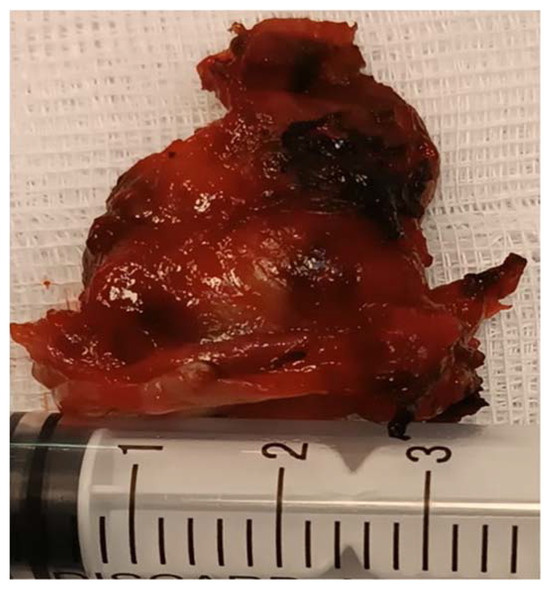

The flexible video laryngoscopy examination revealed a supraglottic mass covering the left aryepiglottic fold and the left arytenoid cartilage, extending to the ipsilateral pyriform sinus. The tumor presented a pronounced vascular draw, having a blueish color. The tumor deviated from the left hemilarynx medially, thus decreasing the movement of the left true vocal fold. The tumor tilted over the laryngeal inlet’s opening, causing breathing difficulties. The right vocal fold has a normal aspect, with normal movement, while the tumor did not obstruct the glottic space (Figure 1).

Figure 1.

The tumor bulges into the laryngeal inlet (the laryngeal inlet is marked by the arrow and the tumor by a star).